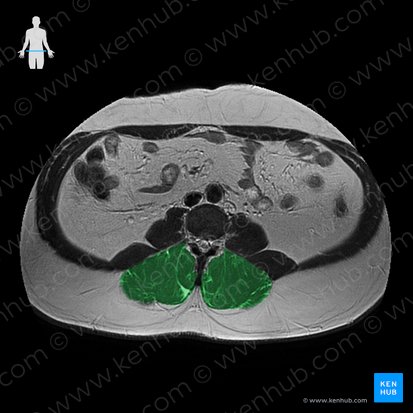

Die Fasern der Mm. levatores costarum breves und longi entspringen an den Querfortsätzen der Halswirbelkörper (HWK) VII bis zum Brustwirbelkörper (BWK) XI. Von dort ziehen sie nach kaudal zu ihrem Ansatz. Die Mm. levatores costarum breves setzen medial des Angulus costae direkt an der kaudal angrenzenden, die Mm. levatores costarum longi an der übernächsten kaudal gelegenen Rippe an.